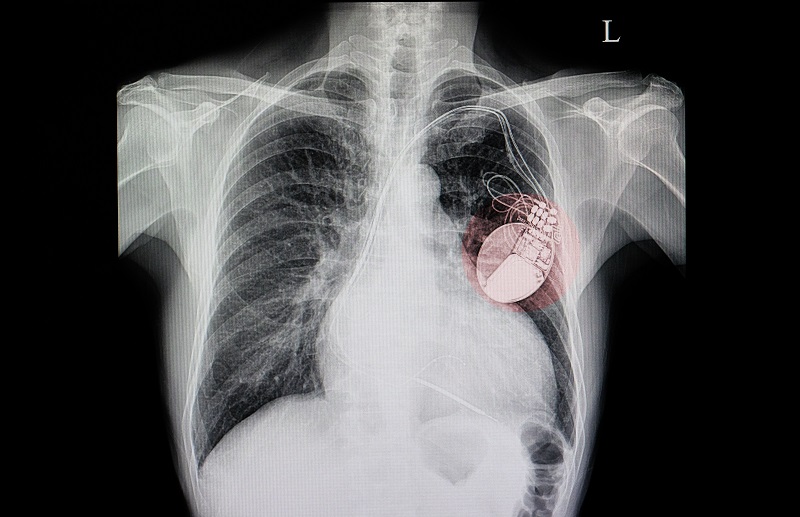

Engedélyezett kereskedés műszívvel

Történelmi engedélyt adott ki az Európai Unió. A Carmat nevű francia orvostechnológiai cég ugyanis 2020 decemberében megkapta az Európai Gazdasági Térségben értékesített termékek megfelelőségét jelző CE jelölést az általa fejlesztett teljesen mesterséges szívre (TAH) – adta hírül iflscience.com portál. Ez azt jelenti, hogy olyan műszív kerülhet értékesítésre, amelyet legalább átmenetileg megkaphatnak szívátültetésre váró betegek. Az akkumulátora akár négy óráig is bírja egy töltéssel, így több korábbi próbálkozással ellentétben a páciens nincs ágyhoz kötve.

Az engedély egyelőre csak olyan esetekre terjed ki, amelyekben a páciens olyan súlyos kétkamrás szívelégtelenségben szenved, hogy semmilyen kórházi kezeléssel nem gyógyítható, és az eszköz beültetését követő 180 napon belül várhatóan valódi szívet kap. Ugyanakkor a Carmat állítása szerint a műszív akár 5 évig is működhet, ami 230 millió szívverést jelent. A cég januárban megkezdi a gyártási kapacitásának bővítését, valamint felveszi a kapcsolatot a potenciális vásárlónak tartott klinikákkal.